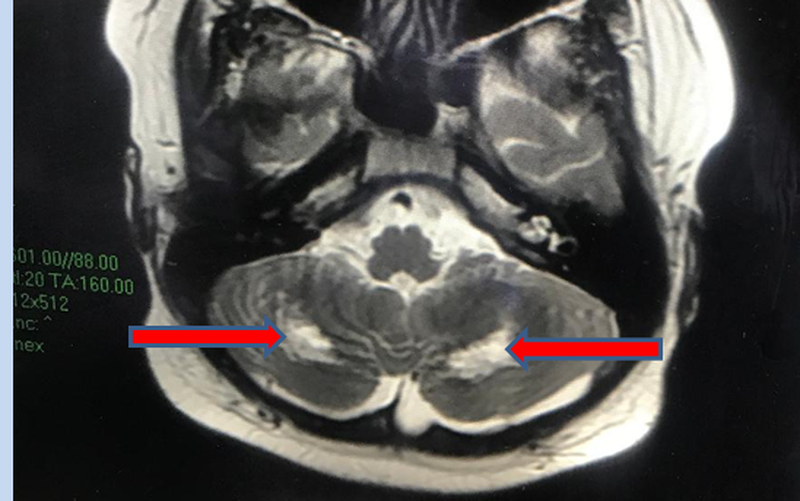

Tuy nhiên, đến tuần thứ 3, bệnh nhi sốt lại, đỏ mắt, đỏ da, có biểu hiện rối loạn phối hợp vận động, xét nghiệm phản ứng viêm trong máu tăng cao trở lại. Các bác sĩ tiến hành chọc dò dịch não tủy xét nghiệm bình thường và chụp MRI não, ghi nhận tổn thương đồi thị hai bên, tổn thương chất trắng của tiểu não.

Các bác sĩ chẩn đoán bệnh nhi mắc hội chứng viêm đa hệ thống, tổn thương não, được điều trị kháng viêm liều cao, kháng đông phòng ngừa tắc mạch.